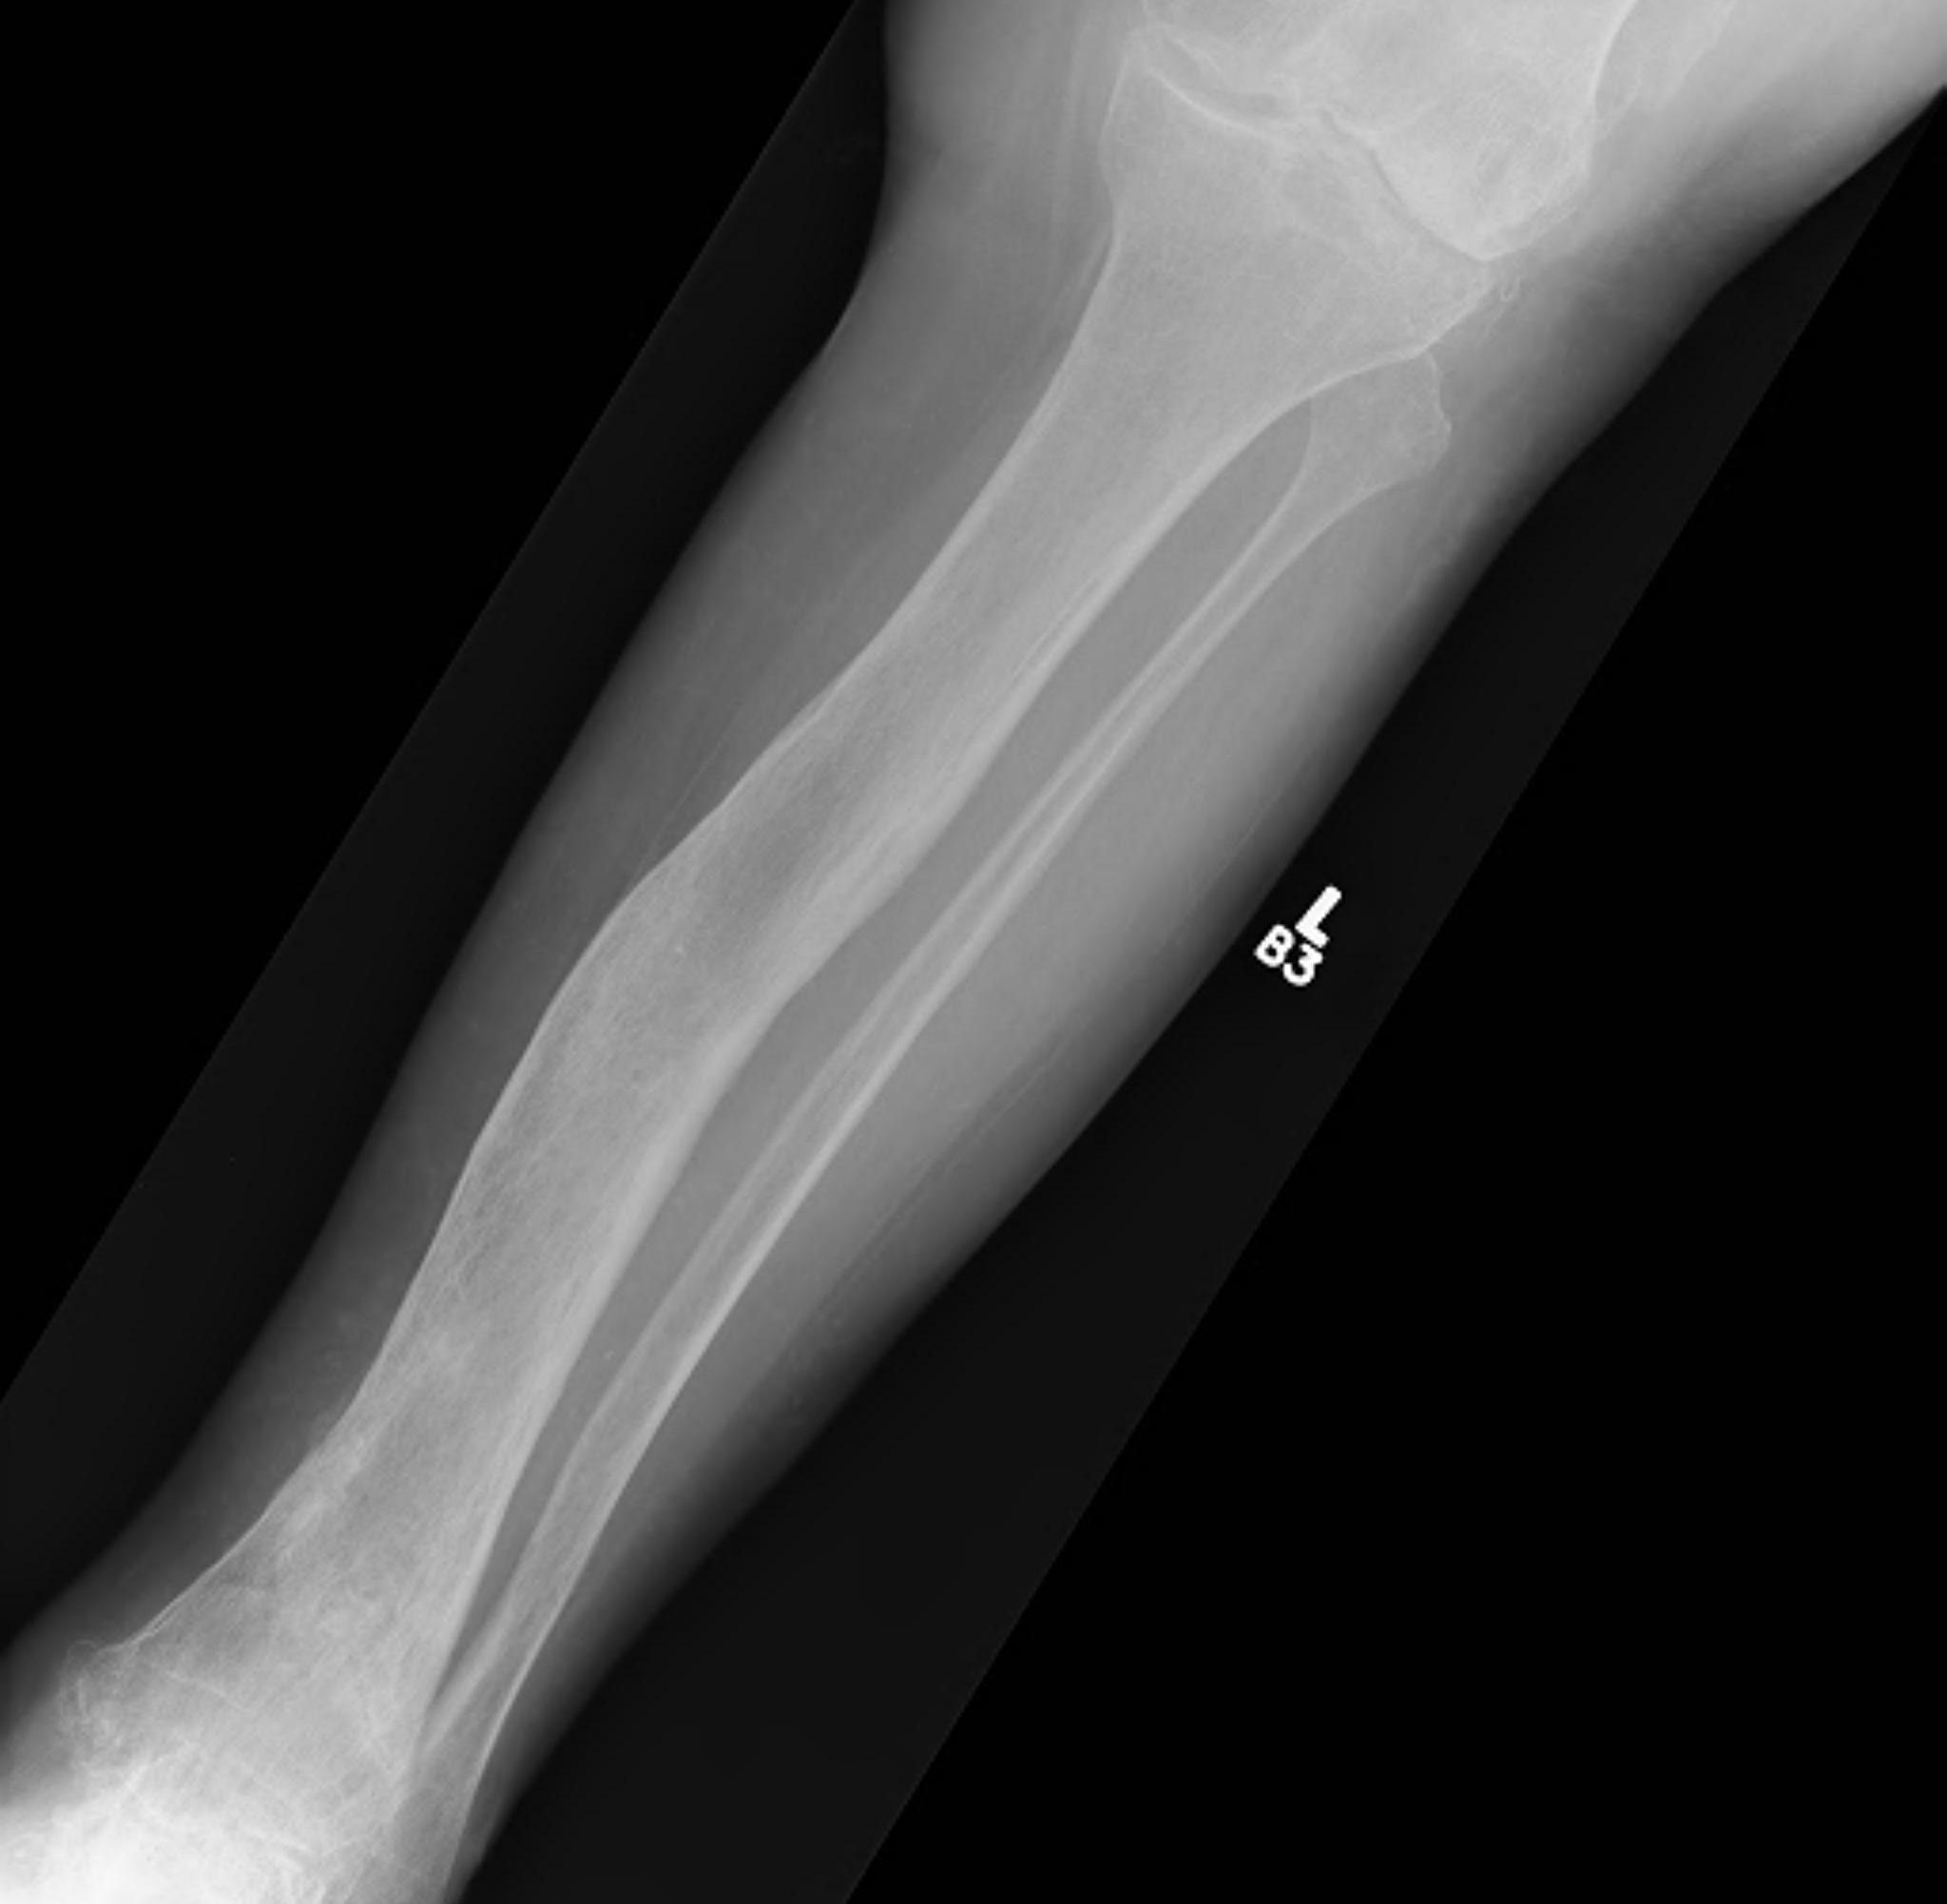

Tibia

Tibia deformity - sabre tibia